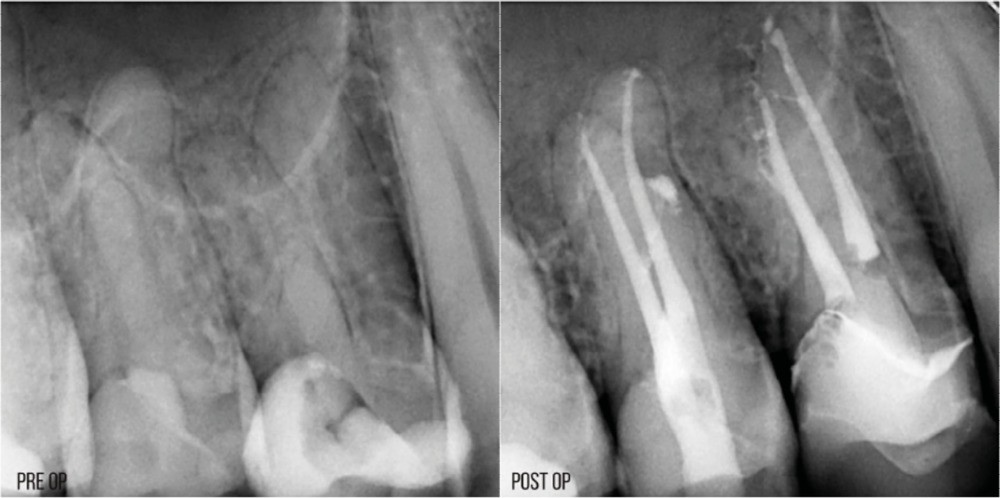

Techniques d’obturation en endodontie raisonnée

La condensation verticale à chaud est la technique d’obturation de référence. Elle nécessite de compacter la gutta-percha jusqu’à environ LT-4 mm avec un fouloir manuel. Avec les préparations conservatrices, il sera parfois difficile d’atteindre cette longueur, même avec le plus fin des fouloirs. Si on prend par exemple une préparation à 25/.04, le diamètre à LT-4 mm sera de 0,41 mm. Le fouloir le plus fin ayant un diamètre de 0,4 mm, il y a de forts risques de contact latéral avec les parois canalaires s’il atteint LT-4 mm, qui pourrait provoquer un effet de coin. Si le canal est courbe, il sera impossible d’amener le fouloir à la longueur souhaitée (fig. 17).

La condensation latérale à froid impose de pouvoir placer un spreader à LT-2 mm. Avec une préparation plus fine, il sera compliqué d’atteindre cette longueur, notamment s’il y a des courbures. C’est aussi une technique qui génère d’importants stress au niveau radiculaire, exposant la racine à un risque plus élevé de fracture [35]. Avec une préparation préservatrice, il y aura plus de contacts entre le spreader et la paroi dentinaire, et potentiellement une augmentation du risque de fracture (fig. 18).